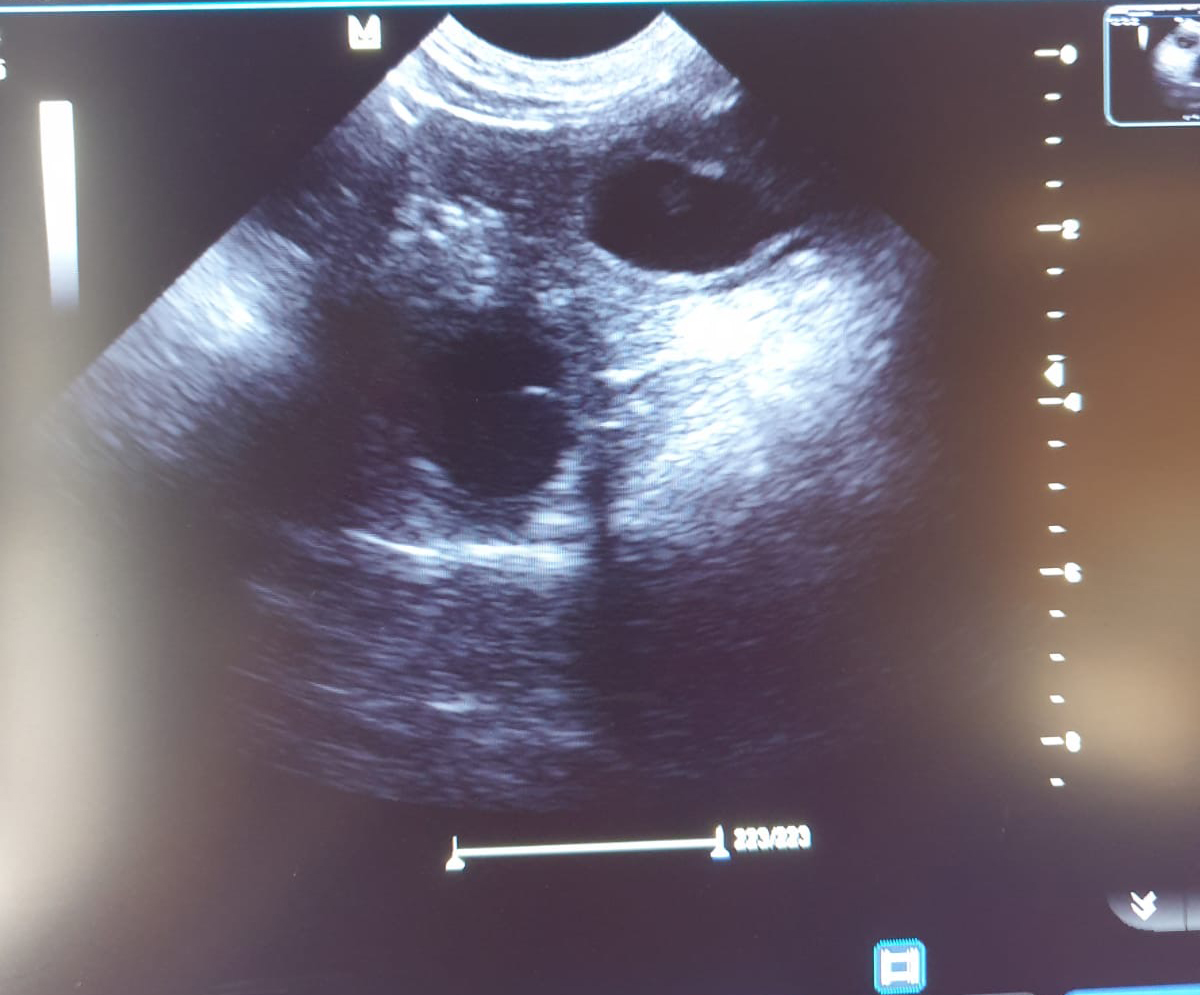

Heute war also der Tag der Tage. Der Tag an dem man Gewissheit bekommt, ob die Hündin aufgenommen hat oder nicht.

Auch wenn in den letzten Tagen einiges für eine Trächtigkeit gesprochen hat, so wollten wir es gerne

von unserer Tierärztin Dr. Insa Gosselaar absegnen lassen.

Beim Ultraschall wurden auf Anhieb einige Fruchtanlagen gesichtet. Die genaue Anzahl wollte ich aber nicht wissen.... ein bisschen Spannung soll uns und den Welpeninteressenten schon noch in den kommenden Wochen erhalten bleiben.  |

Wir freuen uns einfach riesig darüber, dass bald kleine M-Racker den Bagalutenhof besetzen werden.

von unserer Tierärztin Insa Gosselaar absegnen lassen.

Wir freuen uns einfach riesig darüber, dass bald kleine L-Racker den Bagalutenhof besetzen werden.